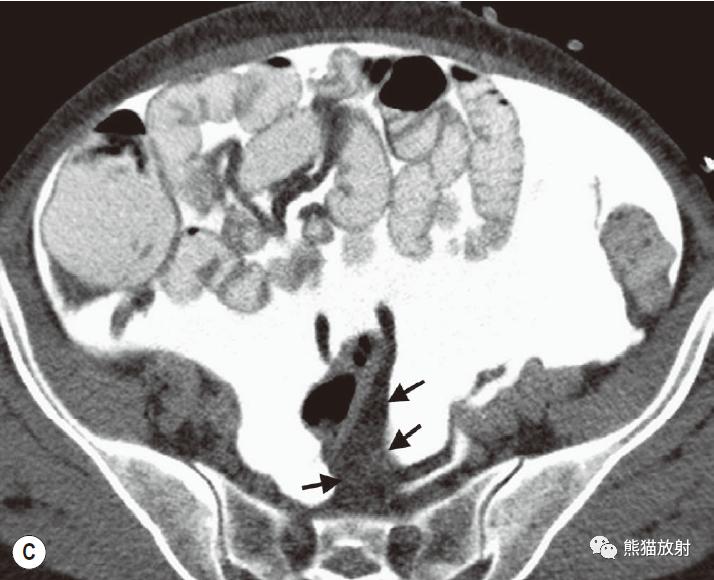

腹内疝:内脏通过腹膜或肠系膜孔突出形成。

包括:十二指肠旁(53%)、盲肠周围(13%)、Winslow孔(8%)、肠系膜和结肠系膜(8%)、乙状结肠间(6%)、吻合口后(5%)疝。

肠系膜疝。 扩张、充满液体的小肠襻丛位于前腹壁下的升结肠侧旁(箭),取代网膜脂肪。充盈的血管及邻近肠系膜模糊,反映了小肠绞窄性梗阻。